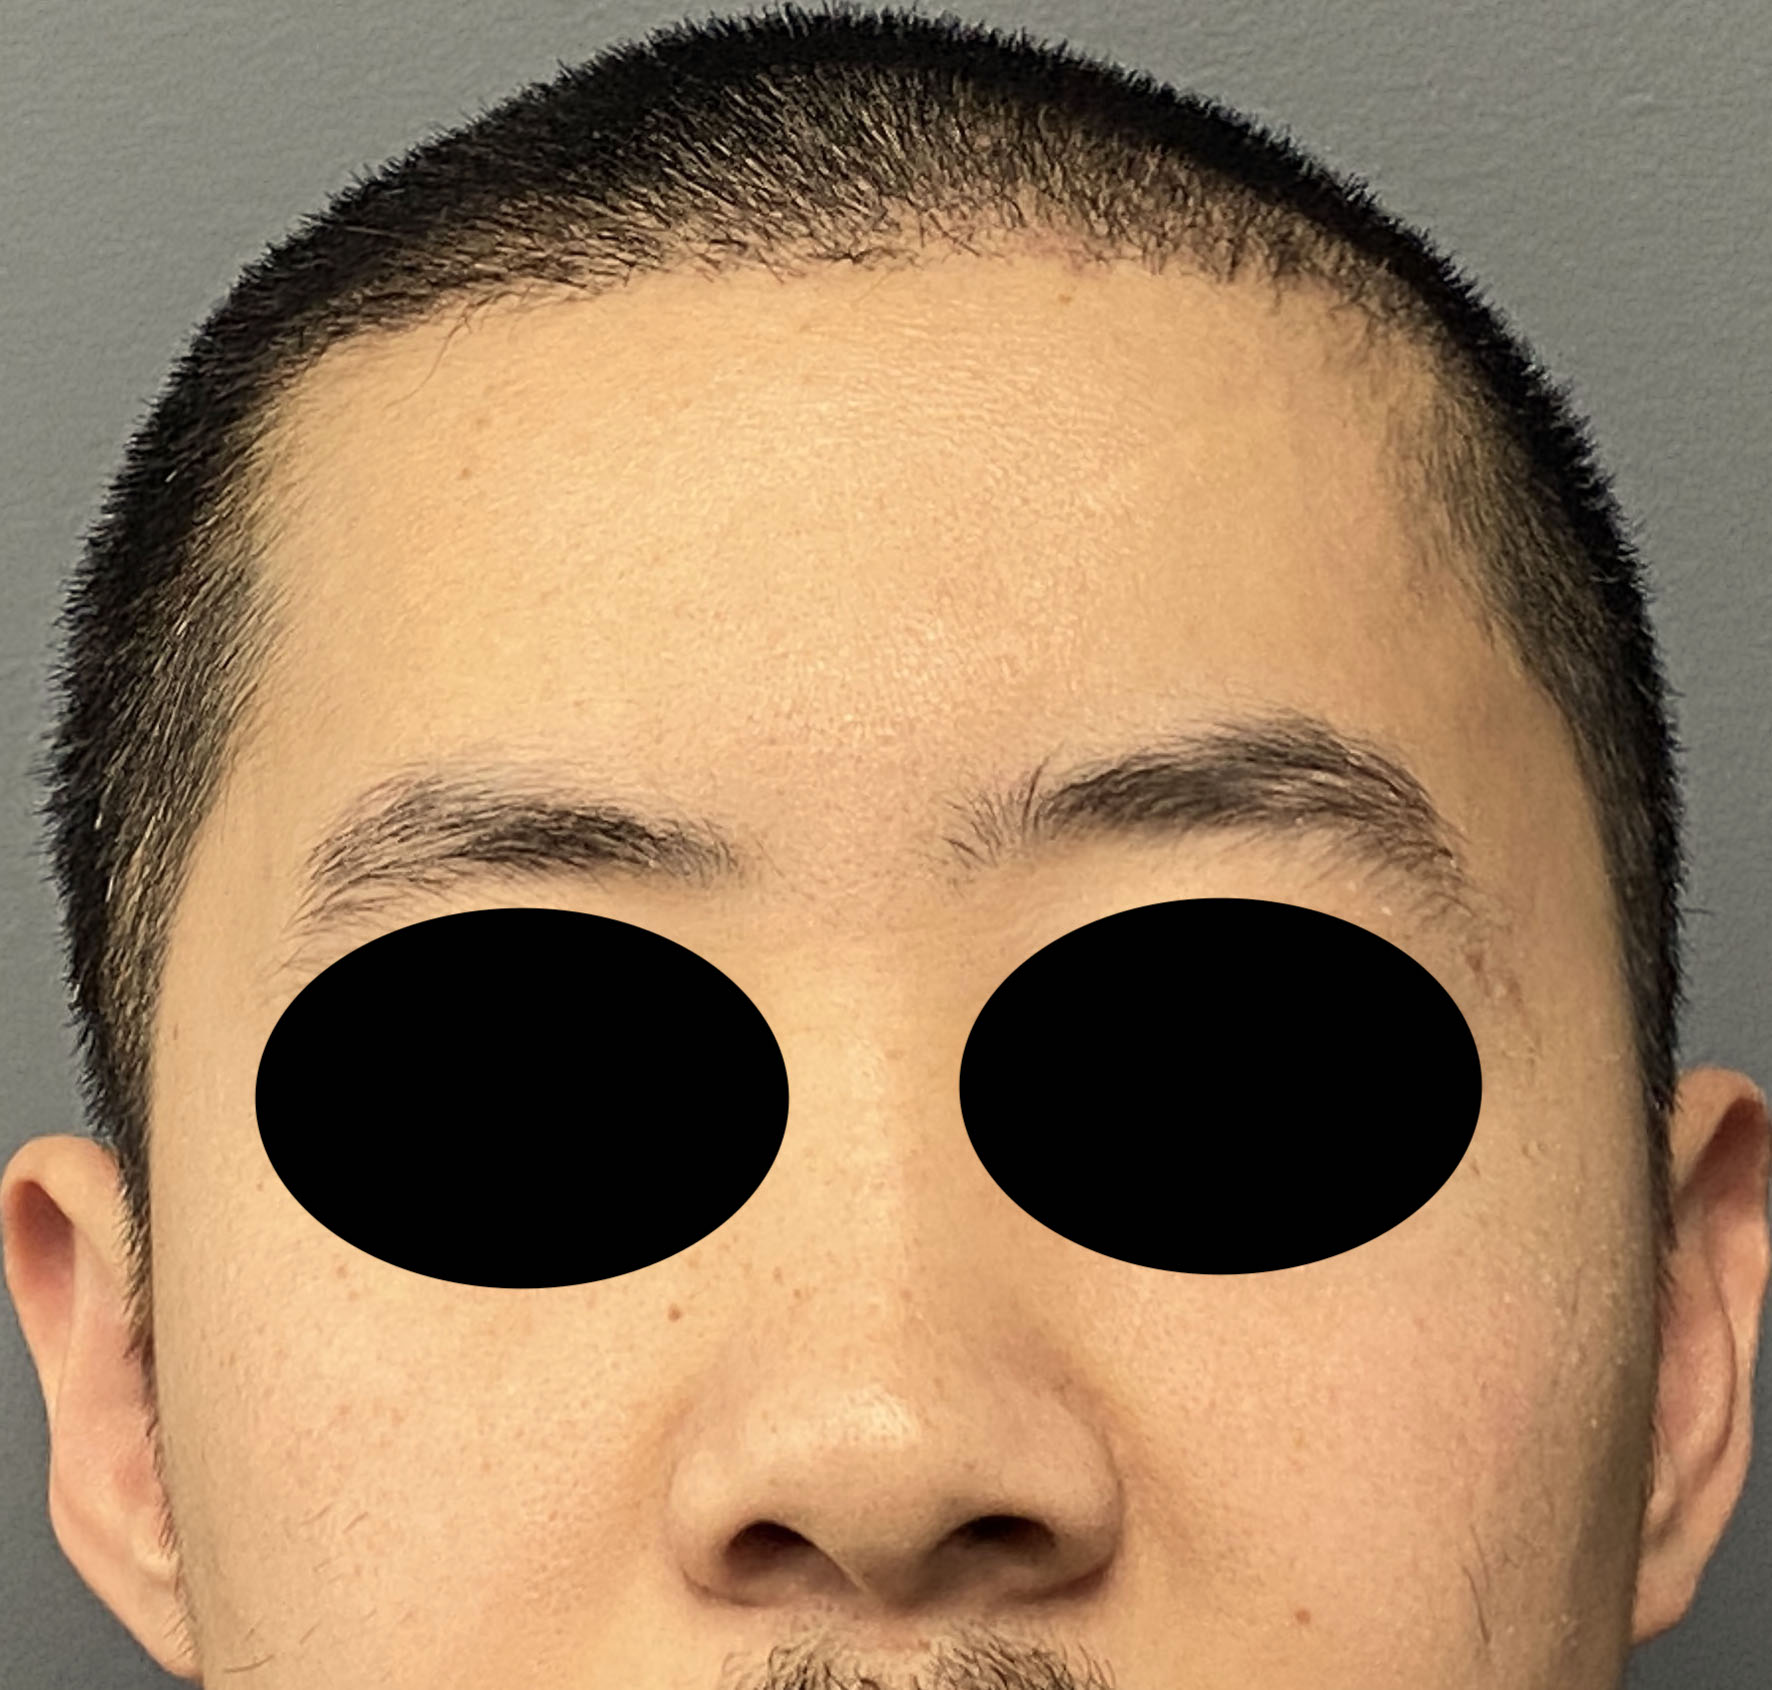

Patient 100

Desire for reshaping of an asymmetric flat back of the head in a shaved head male.

A combined back of the head reshaping procedure was done with a custom skull implant, sagittal ridge reduction and a right temporal muscle reduction.

Desire for reshaping of an asymmetric flat back of the head in a shaved head male.

A combined back of the head reshaping procedure was done with a custom skull implant, sagittal ridge reduction and a right temporal muscle reduction.